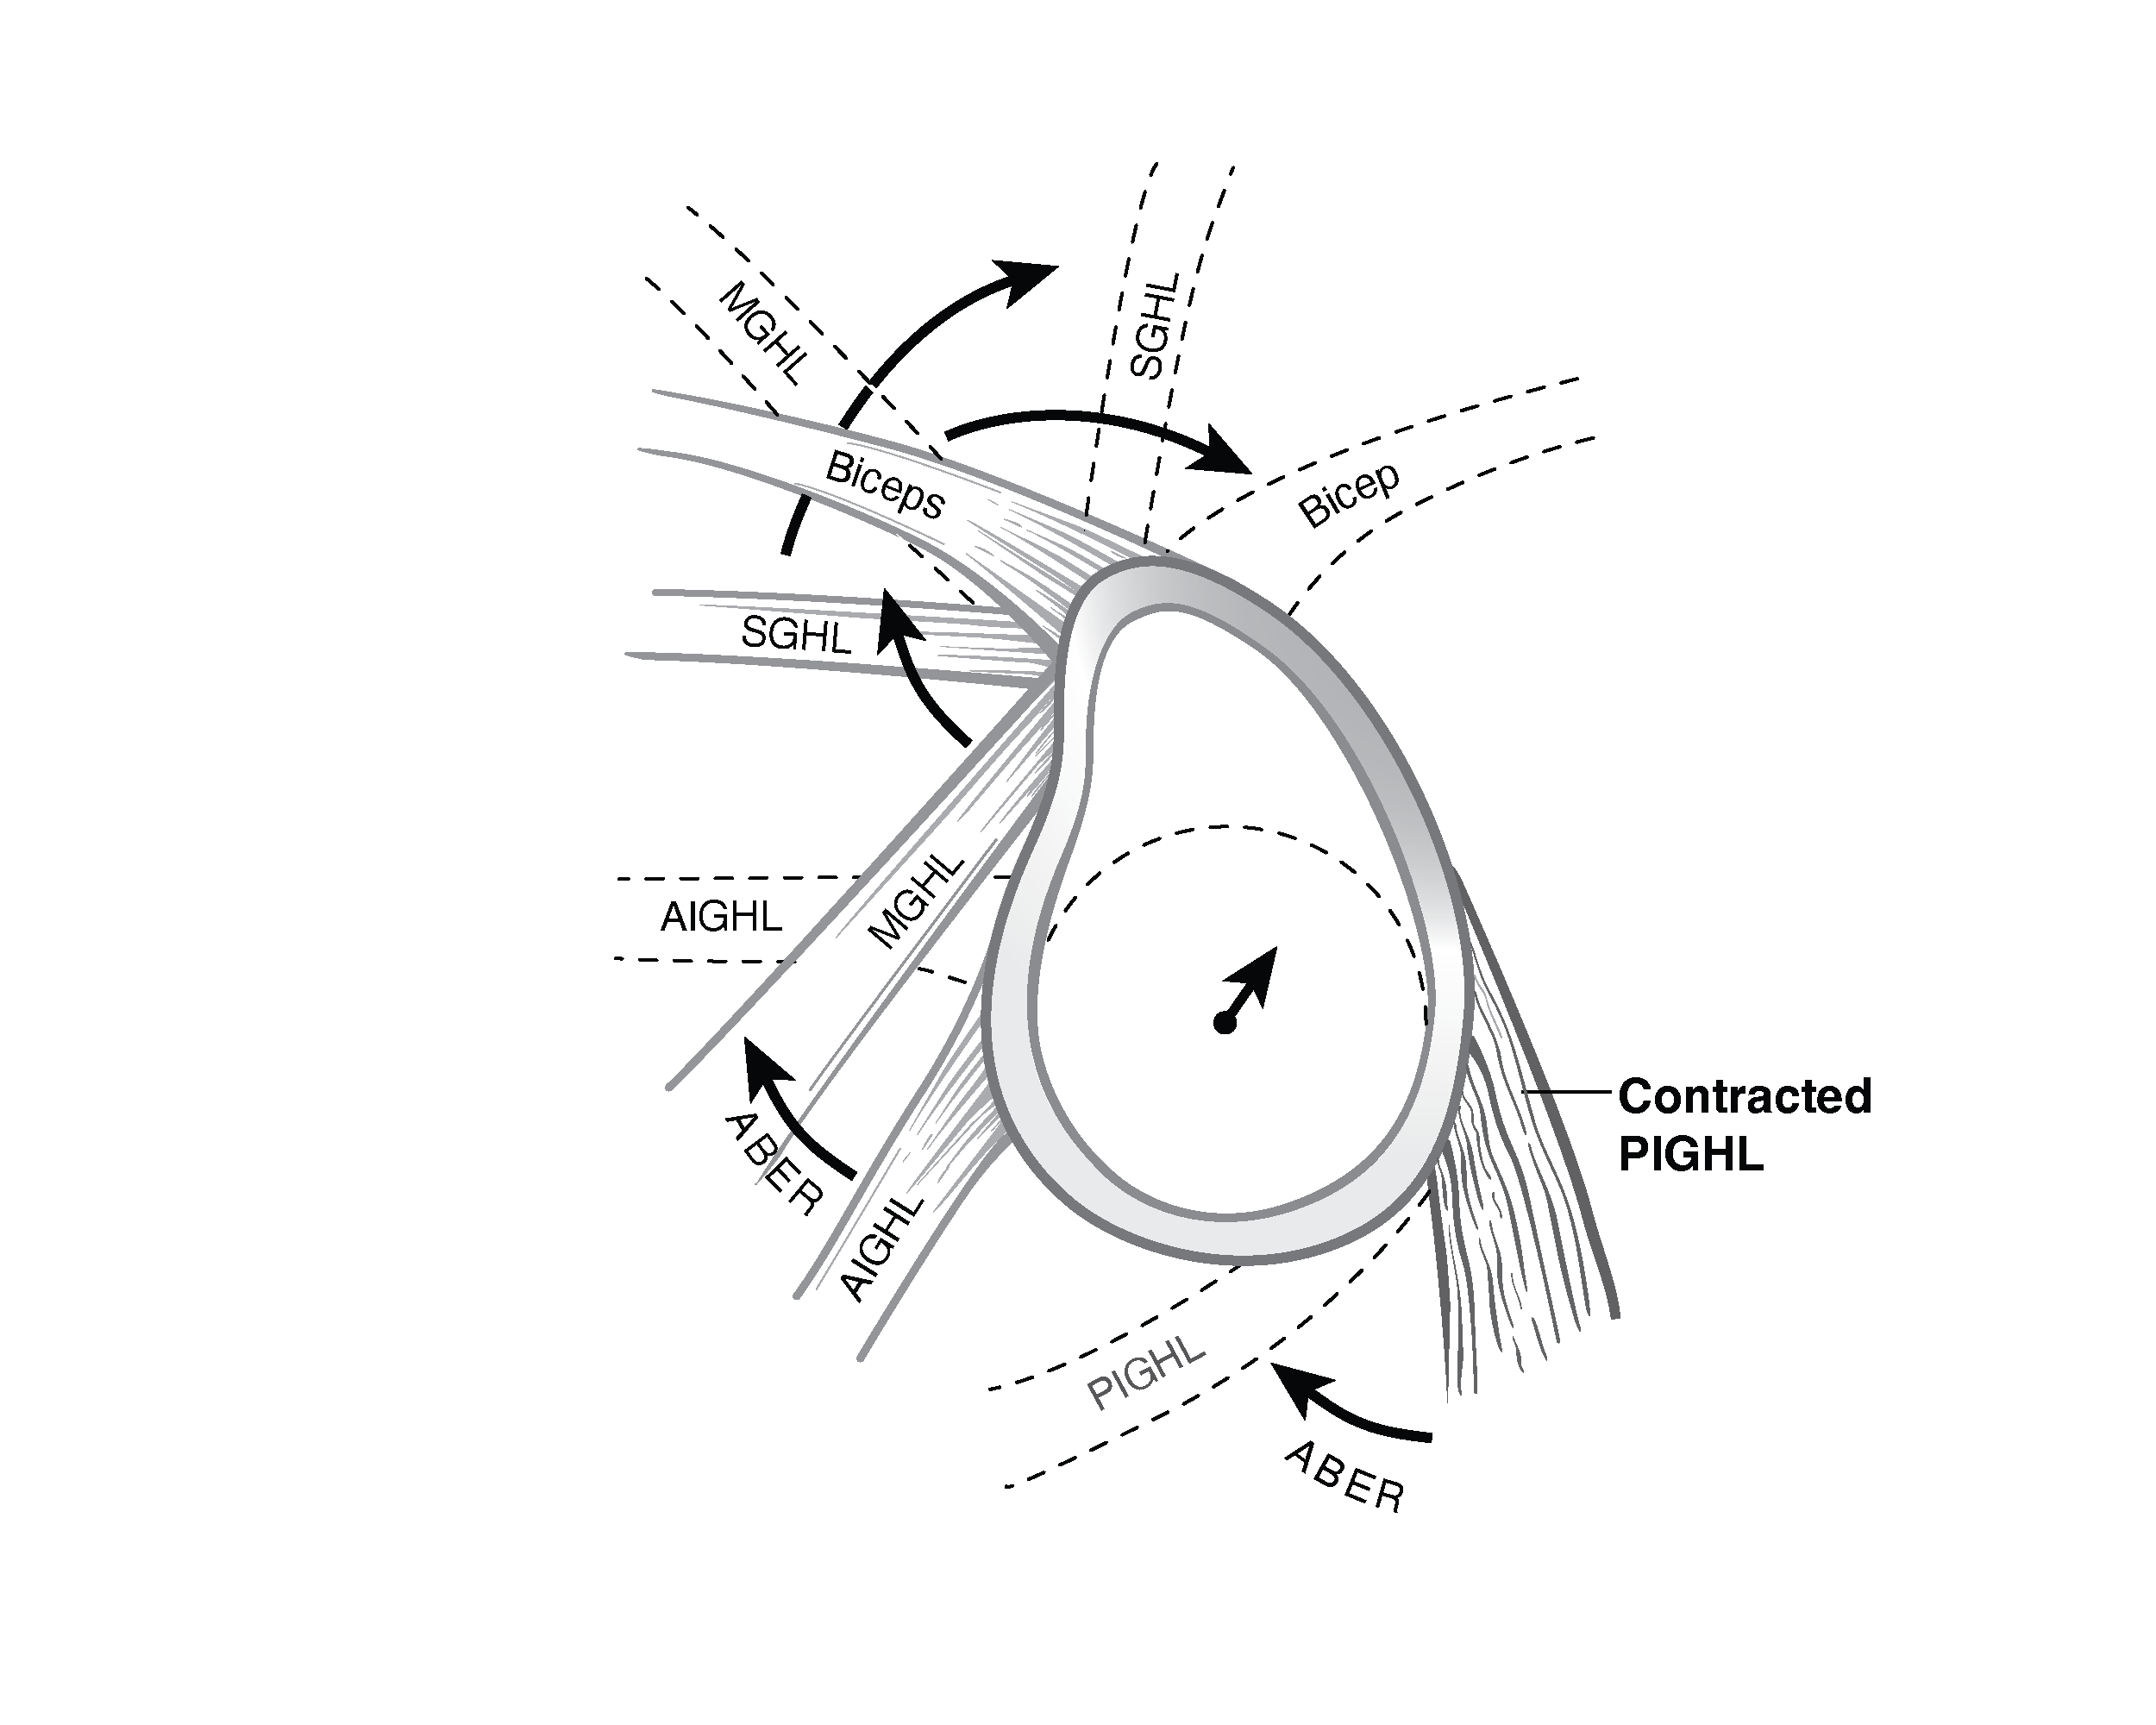

Surgical illustrations visually depict operative techniques, surgical anatomy, and complex procedures. They are created with high anatomical accuracy and serve as a visual bridge between complex surgical knowledge and learners, clinicians, or patients.